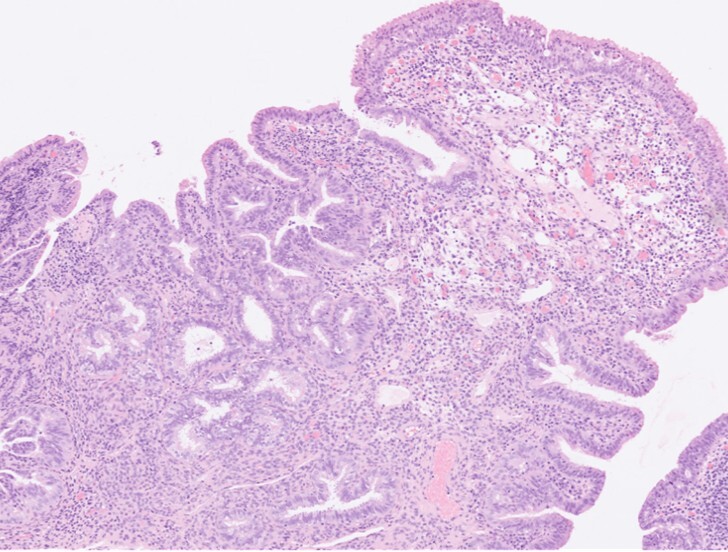

Histopathological examination (Figures 3 & 4) showed polypoid mucosal changes with papillary projections and cystic, dilated tubules lined by fallopian tube-type epithelium. No nuclear atypia, increased mitoses, or other Mullerian elements such as endocervical or endometrial tissue were identified. Immunohistochemistry (Figures 5-10) demonstrated positivity for CK7, oestrogen receptor, and progesterone receptor, while GATA3, P63, and CK20 were negative.

Radiological findings are often nonspecific, making pre-operative diagnosis challenging. Histological examination is essential for confirmation. It reveals tubal or papillary structures lined by characteristic fallopian tube-type epithelium with three types of cells, which include ciliated cells, mucinous cells, and intercalated cells, located in the lamina propria or muscularis propria of the urinary bladder wall. Immunohistochemistry findings are identical to the fallopian tube with CK7, oestrogen, and progesterone receptor positivity and absence of urothelial markers like GATA3, uroplakin II, uroplakin III and P63.

It is important to differentiate endosalpingiosis from other benign and malignant conditions that can mimic its appearance macroscopically and microscopically. Differential diagnosis in histology includes cystitis glandularis, nephrogenic adenoma, urachal remnants, and adenocarcinoma of the urinary bladder. Immunohistochemistry is a valuable tool in establishing the diagnosis in problematic cases, especially when the fallopian tube-type epithelial elements extends to the muscularis propria mimicking an invasive carcinoma.